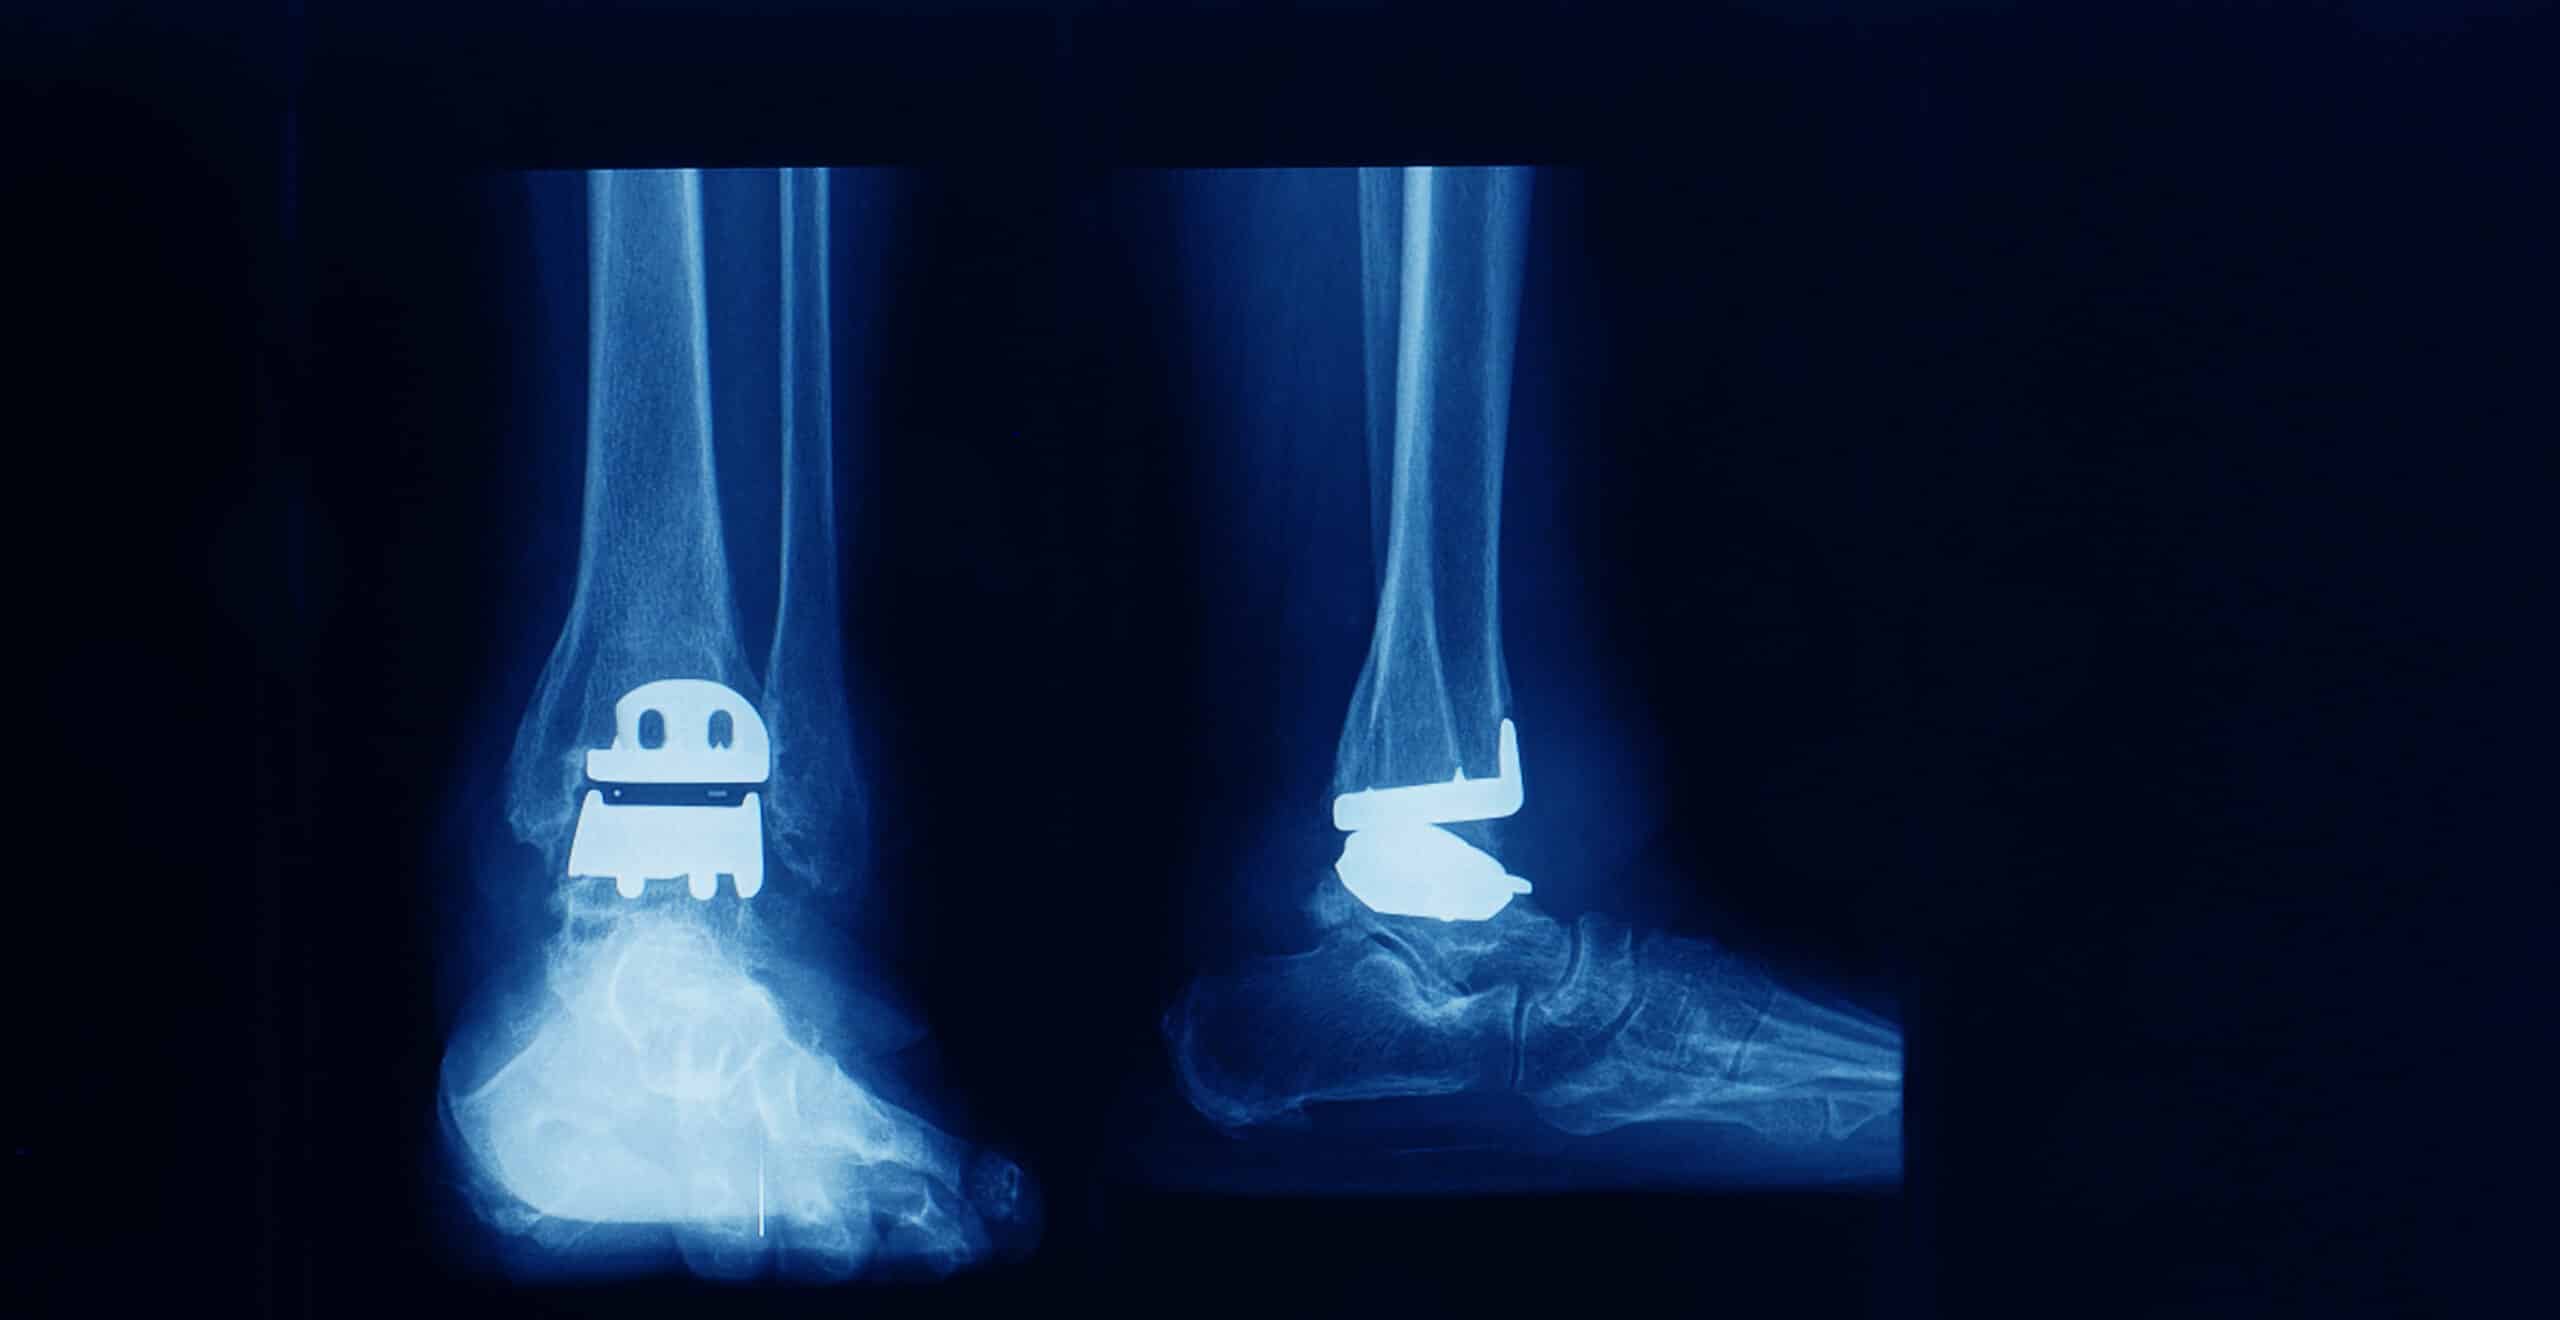

One reason that a patient will continue to have pain after ankle replacement is joint loosening. The ankle replacement is no longer stable and the patient suffers from the same type of ankle instability that they had suffered from before the surgery. The difference here is that the surviving ligaments, tendons and other soft tissue are now being stretched as the ankle becomes wobbly. The other reason for pain after ankle replacement is the problem of nerve damage caused by the surgery. Let’s look at what the surgeons have to say and then we can discuss the possible treatment options that may allow some people to avoid a revision ankle replacement or an ankle fusion.